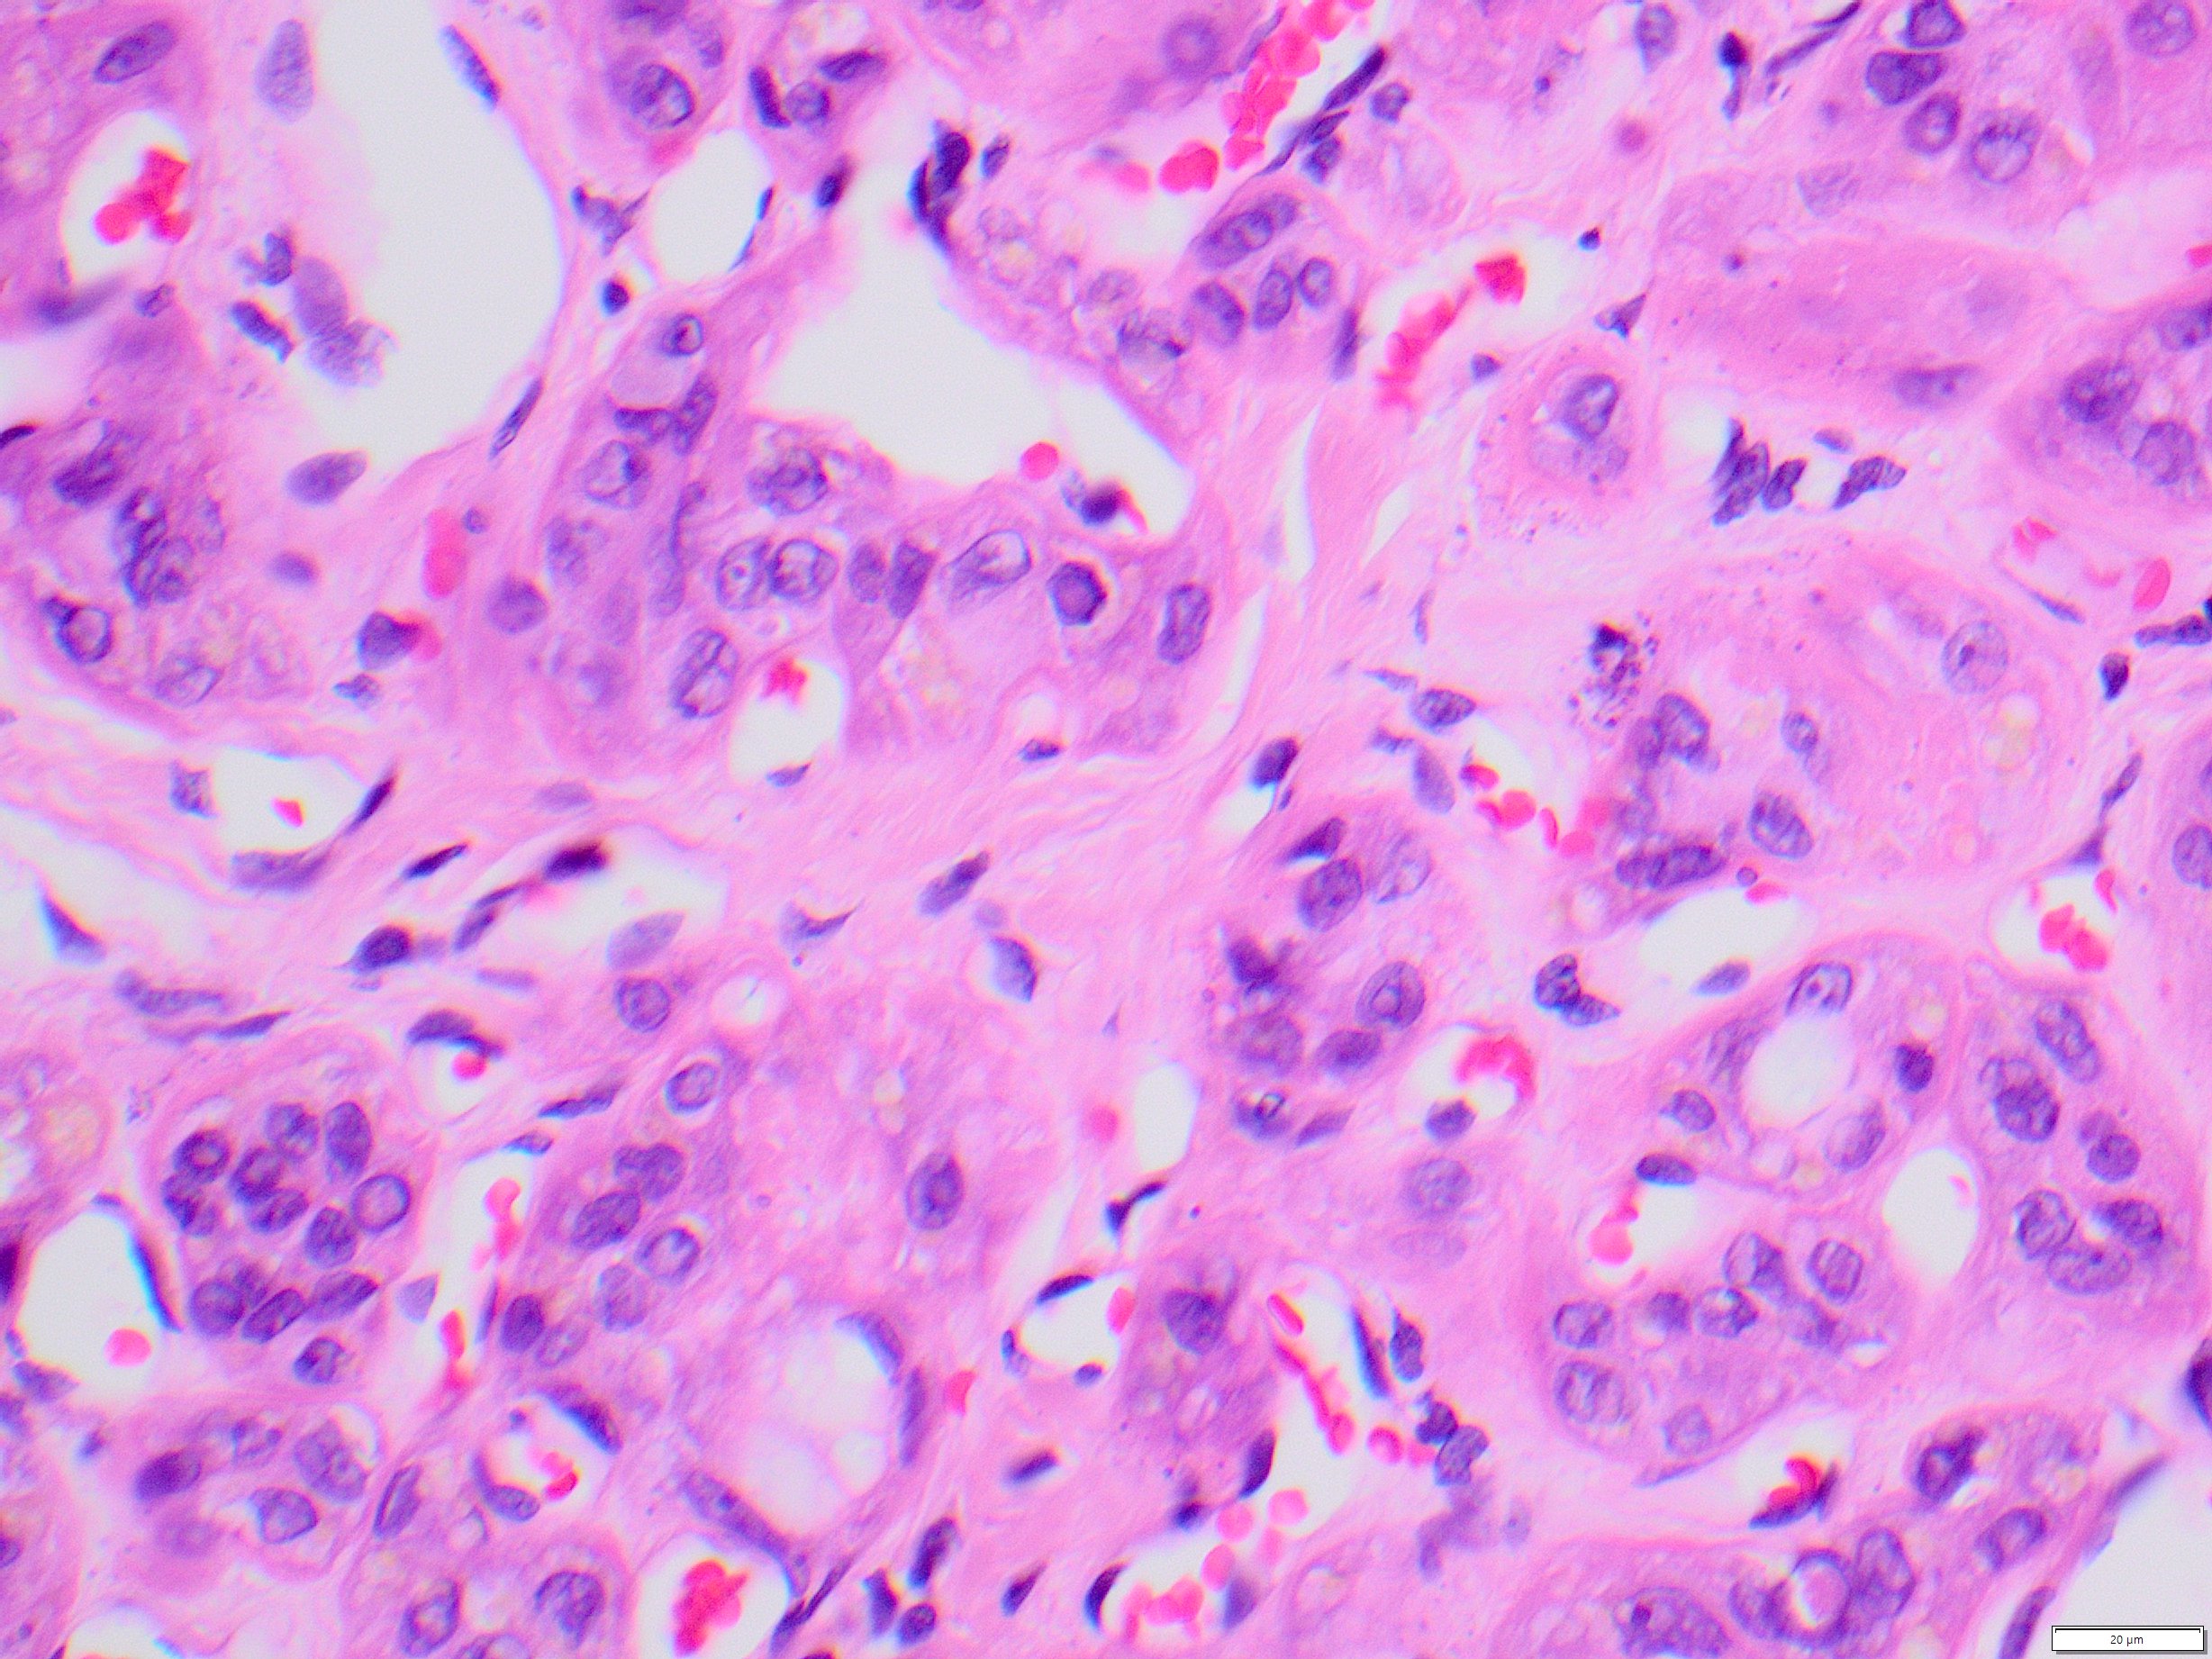

A 69-year-old woman presents with a thyroid mass. Representative sections of the thyroidectomy specimen are shown.

Sections show a tumor with trabecular and organoid architecture with cystic spaces and prominent fibrovascular stroma. Calcifications are also present. Tumor cells have abundant granular cytoplasm with nuclear grooves, pseudoinclusions, and pale chromatin. Some cells also have yellow cytoplasmic inclusions. These features are consistent with hyalinizing trabecular tumor/adenoma. Though papillary nuclear features are present, these tumors tend to behave as benign neoplasms. RET/PTC translocations have been identified in some of these tumors. However, BRAF mutations have not been found. TERT promoter mutations are strongly associated with malignant neoplasms of the thyroid and confer a poor prognosis.